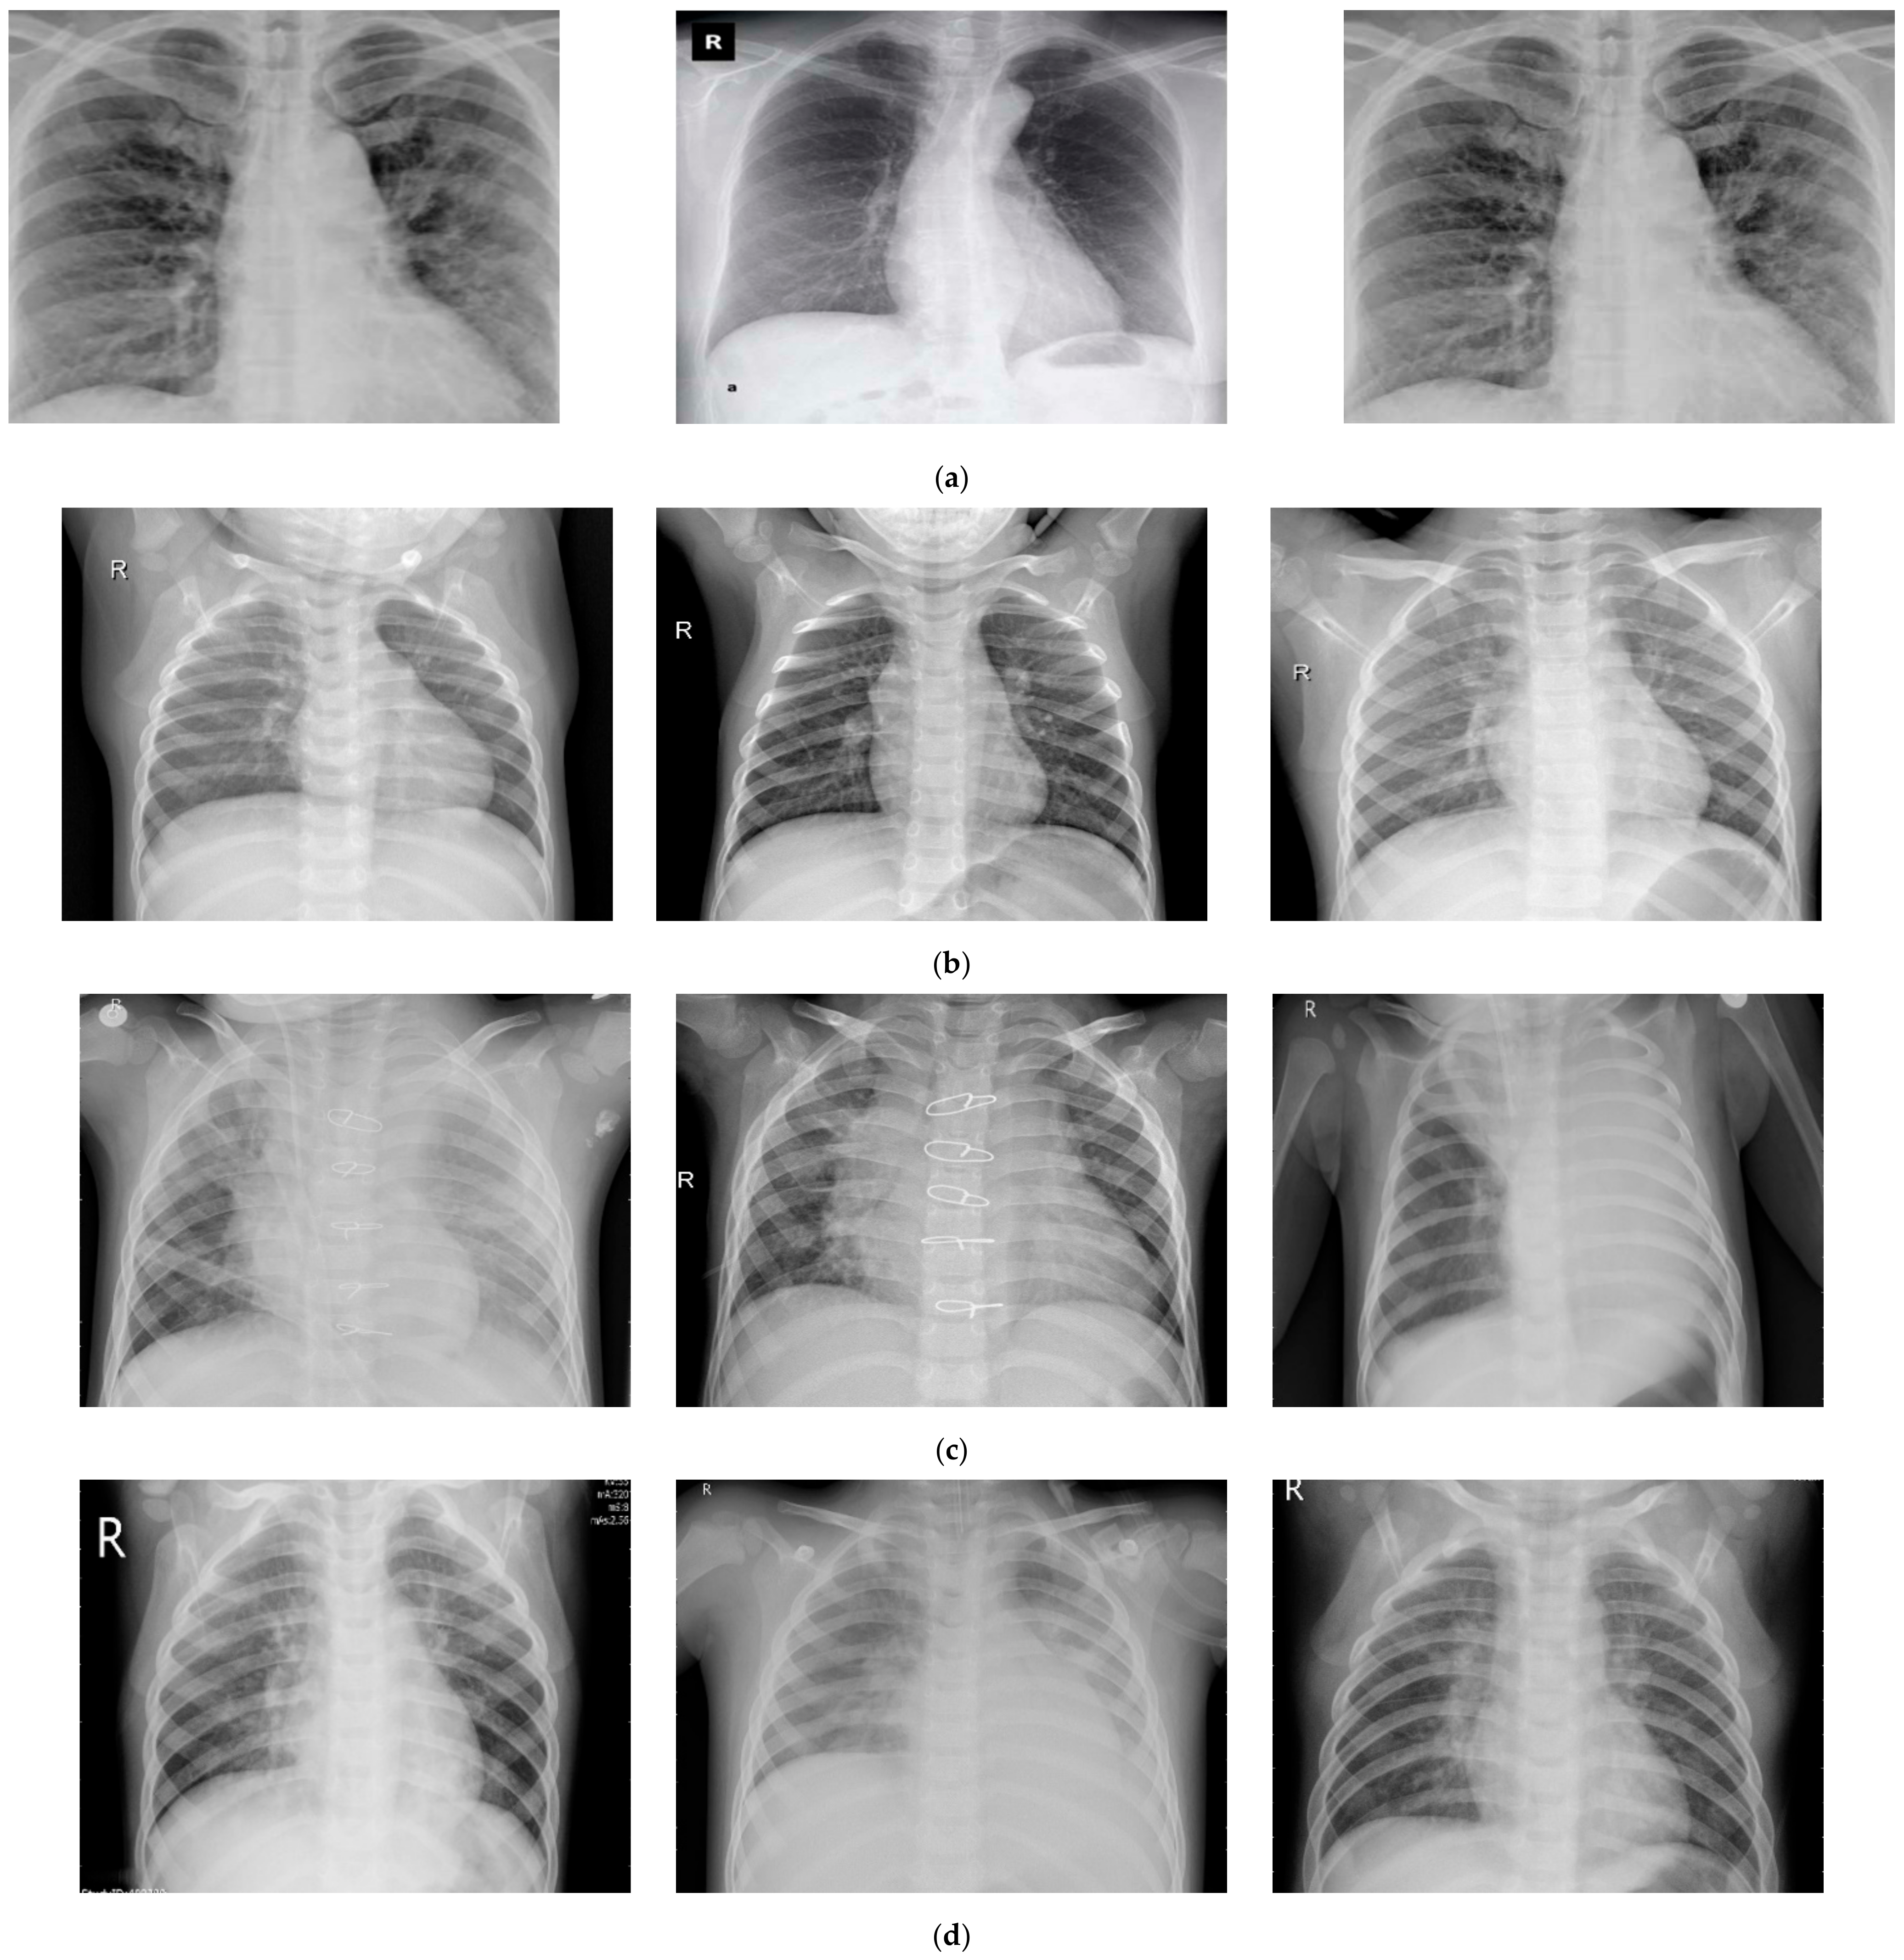

3.1. Data Visualization